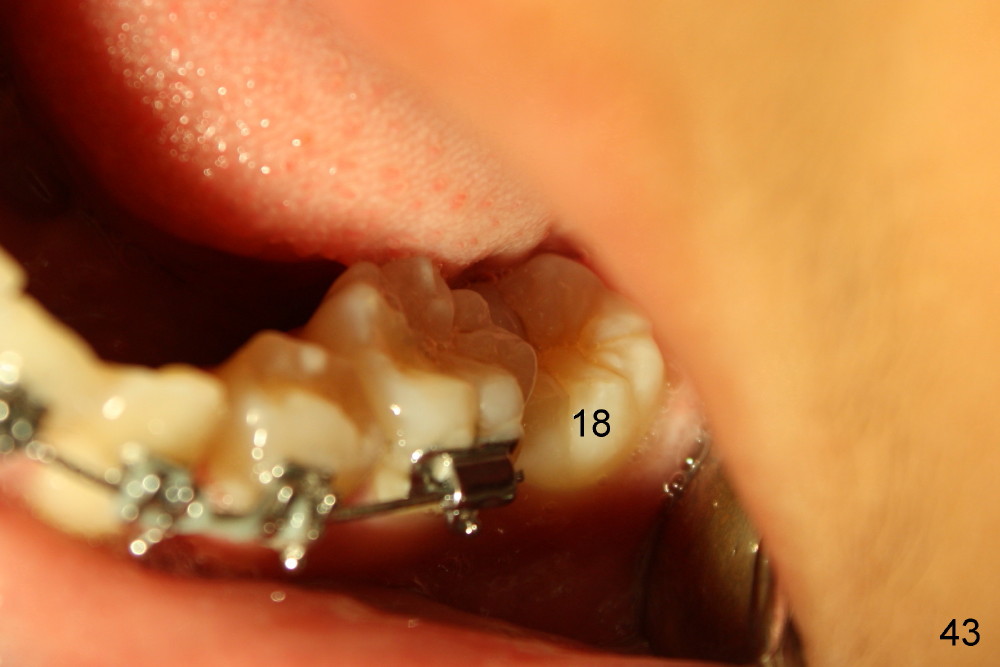

Two months later, LL7 (#18 in Fig.53,54) appears to be uprighted by itself (probably due to mesialization of the teeth mesial to it); a bracket is placed with .012 niti wire. No power chains are used to close the diastemata among the upper teeth, since the anterior overjet is minimal. A rotation wedge is placed in the distal wings of #27 to fix rotation. Is it right?